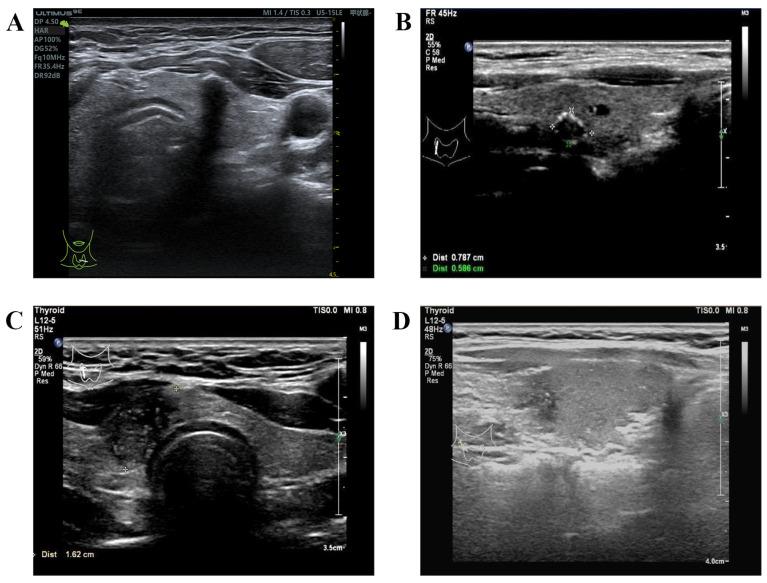

临床特征及多模态超声对甲状腺乳头状癌中央区淋巴结转移的预测价值

Predictive Values of Clinical Features and Multimodal Ultrasound for Central Lymph Node Metastases in Papillary Thyroid Carcinoma.

Papillary thyroid carcinoma (PTC), the predominant pathological type among thyroid malignancies, is responsible for the sharp increase in thyroid cancer. Although PTC is an indolent tumor with good prognosis, 60-70% of patients still have early cervical lymph node metastasis, typically in the central compartment. Whether there is central lymph node metastasis (CLNM) or not directly affects the formulation of preoperative surgical procedures, given that such metastases have been tied to compromised overall survival and local recurrence. However, detecting CLNM before operation can be challenging due to the limited sensitivity of preoperative approaches. Prophylactic central lymph node dissection (PCLND) in the absence of clinical evidence of CLNM poses additional surgical risks. This study aims to provide a comprehensive review of the risk factors related to CLNM in PTC patients. A key focus is on utilizing multimodal ultrasound (US) for accurate prognosis of preoperative CLNM and to highlight the distinctive role of US-based characteristics for predicting CLNM.

甲状腺乳头状癌(PTC)是甲状腺恶性肿瘤中最主要的病理类型,是导致甲状腺癌急剧增加的原因。尽管PTC是一种预后良好的惰性肿瘤,但60%-70%的患者仍有早期颈部淋巴结转移,通常发生在中央区。鉴于这种转移与总体生存率降低和局部复发有关,是否存在中央区淋巴结转移(CLNM)直接影响术前手术方案的制定。然而,由于术前检查方法的敏感性有限,术前检测CLNM具有挑战性。在没有CLNM临床证据的情况下进行预防性中央区淋巴结清扫(PCLND)会带来额外的手术风险。本研究旨在全面综述PTC患者中与CLNM相关的危险因素。重点是利用多模态超声(US)对术前CLNM进行准确预后评估,并强调基于超声特征在预测CLNM方面的独特作用。